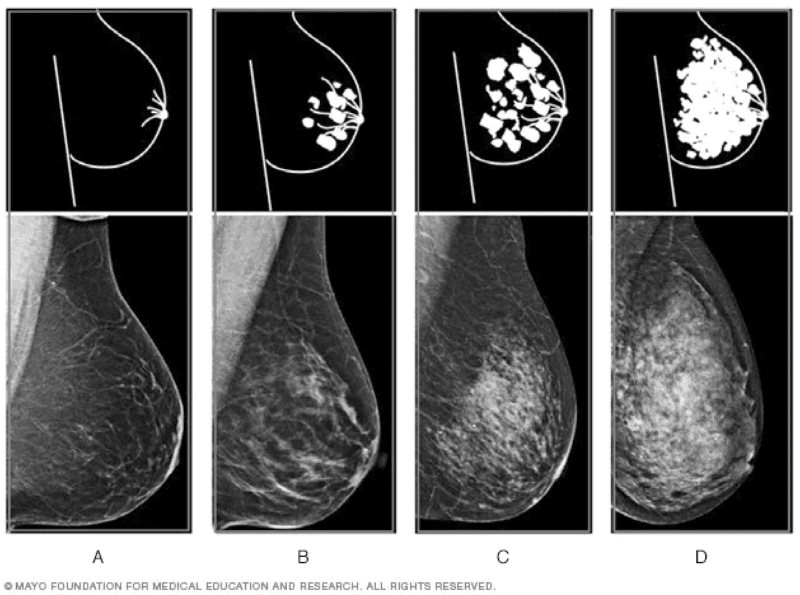

En una mamografía, el tejido mamario no denso se ve oscuro y transparente, mientras que el tejido mamario denso se ve como una zona blanca sólida, lo que hace que resulte difícil ver a través de él.

No se sabe con certeza por qué algunas mujeres tienen un tejido mamario denso y por qué otras no, pero de acuerdo con Mayo Clinic y con la Biblioteca Nacional de Medicina de Estados Unidos, esto se presenta con frecuencia en las mujeres jóvenes y con poca grasa corporal.